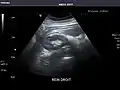

Abdominal Ultrasound (Full Exam)

STRUCTURED REPORT

(Technique: Transabdominal ultrasonography; Device: Toshiba Aplio XG)

Liver: Diffusely homogeneous and normal in echogenicity. No focal mass or contour nodularity. No intrahepatic biliary ductal dilatation.

Portal Vein: Patent main portal vein.

Gallbladder: No stones, wall thickening, or pericholecystic fluid.

Common Bile Duct: Nondilated measuring 1.3 mm at the level of the porta hepatis.

Pancreas: Visualized portions unremarkable.

Spleen: Normal in size.

Kidneys: Right and left kidneys measure 11.5 cm and 12 cm in length respectively. No hydronephrosis. Small left lower pole kidney cyst.

Ascites: None.

Aorta: Visualized portions normal in caliber, 16 x 15 mm.

IVC: Normal.

IMPRESSION:

Normal abdominal ultrasound.

Right kidney -

Left kidney -